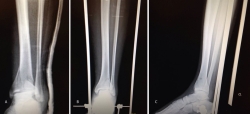

2. Fractura espiroidea con afectación articular, reducida mediante medios externos bajo control radioscópico y fijada con tornillos percutáneos.

Bajo anestesia raquídea e isquemia en la raíz del miembro afecto, colocamos al paciente en decúbito supino con la pierna en férula de Braun y una tracción en el tobillo con vendas o con sistema de tracción suministrado por casas comerciales.

Realizamos los portales artroscópicos habituales en función de la situación de los extremos óseos de la fractura y practicamos un procedimiento idéntico al anterior: lavado, desbridamiento e identificación del foco de fractura (Figuras 12 a 16).

Figura 12. Caso 2: fractura espiroidea con afectación articular. Posicionamiento en férula de Braun. Tracción con vendas. Realización de portales.

Figura 13. Posteriormente, realizamos la limpieza del foco con cucharilla y la reducción del mismo mediante pinzas de cóndilo bajo control radioscópico/artroscópico, y fijación provisional con agujas de Kirschner.

Figura 14. A continuación, se realiza la medición y colocación secuencial de los tornillos.

Figura 15. Por último, se procede a la colocación definitiva de los tornillos.

Figura 16. Resultado final a los 4 meses.